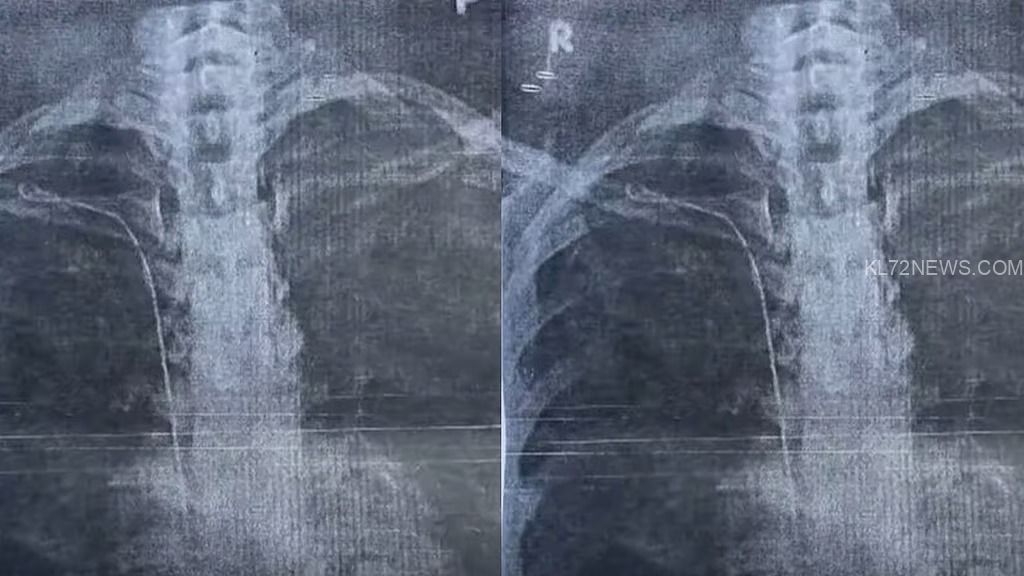

ചികിത്സക്കിടെ യുവതിയുടെ നെഞ്ചില്‍ ട്യൂബ് കുടുങ്ങി, റിപ്പോര്‍ട്ട് തേടി ഡിഎംഒ